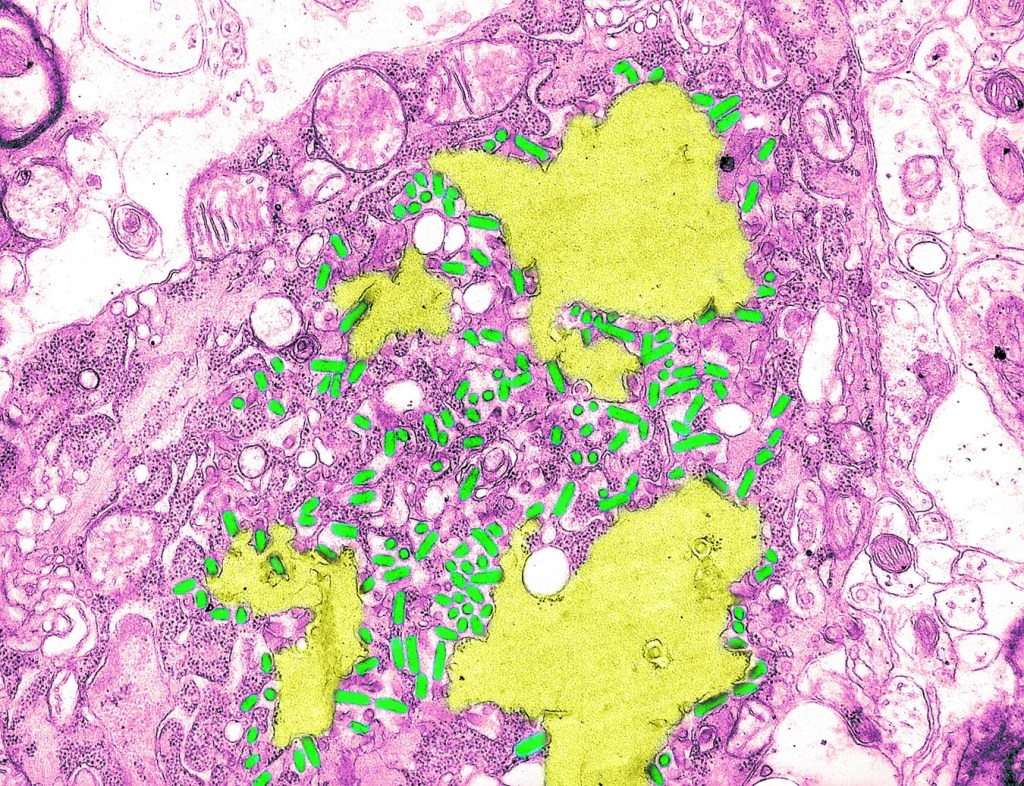

Crédito: Science History Images